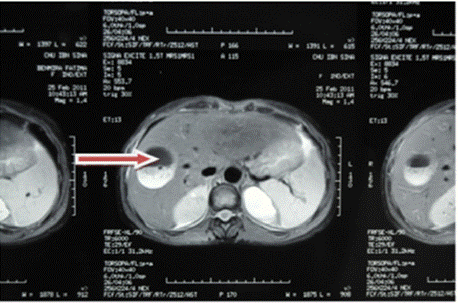

Ultrasound of the right liver (anterior sector) revealed a heterogeneous cystic image with a thin wall, suggestive of a type IV hydatid cyst. Abdominal CT confirmed a multiloculated cystic lesion containing fatty, calcified, and fluid components, suggestive of a hepatic teratoma. An MRI scan further supported the diagnosis, showing a grossly oval lesion in the hepatic dome measuring 57 × 48 mm. The lesion contained a fluid level with a supernatant displaying T1 hypersignal, T2 hyposignal, and a dependent portion in T1 and T2 isosignal, without enhancement after gadolinium injection — findings suggestive of a modified hydatid cyst.

Figure 4: Red arrow: well-defined rounded lesion in segment VIII with

probable cystic NHA image.